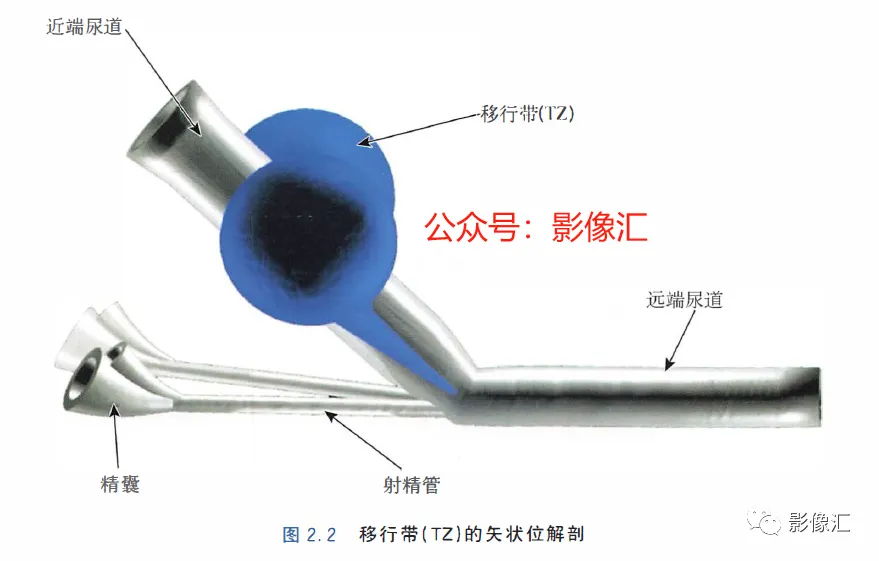

McNeal解剖模型认为前列腺根据周围不同结构环绕的关系而分为四个区域。尿道是描述整个前列腺区域解剖结构的解剖学标志。尿道由近端和远端尿道两个部分组成,每个部分约15mm长,由精阜分界。在精阜处,近端和远端尿道的走行呈35°。尿道壁由纵向走行的平滑肌纤维组成。围绕该内层的纵向肌肉层,是一层环形走行的肌层。两层平滑肌构成所谓的尿道内括约肌(IUS),其从膀胱颈延伸到尿道膜部的末端。IUS在膀胱颈的近端水平处最厚,随其向尿道膜部延伸,厚度逐渐减小。尿道膜部完整地被IUS环绕。在其前侧,前列腺内的lUS与前列腺肌性间质(AFMS)融合。两射精管走行方向与远端尿道平面平行,其开口于尿道腔内的前列腺小囊。移行带在前列腺组织中约占5%,构成两叶分别位于近端尿道两侧。其导管系统平行于尿道平面走行,止于精阜,射精管开口的近侧。移行带毗邻外周带,中央带和前列腺肌性间质,构成所谓的外科手术包膜,也就是说,确定了前列腺剜除术的外科手术平面。移行带和尿道周围腺体组织是良性前列腺增生(BPH)的发生部位。前列腺癌发生在移行带的比例为10%~20%。中央带在前列腺腺体组织中约占25%。其在前列腺底部形成金字塔形或锥形结构,在精阜水平处变窄至顶点。中央带的导管在射精管开口的两侧呈放射状走行。精囊和输精管穿入中央带形成射精管形似“精囊喙”。此区域由于缺乏前列腺包膜而成为解剖薄弱区。与射精管延续的中央带及伴行的筋膜和淋巴血管组织称为前列腺嵌入部(invaginated extraprostatic space,IES)。这是另一个解剖学上的薄弱区域,因此中央带疾病容易沿此区域播散。中央带相对发病率较低,发生在中央带的前列腺癌占5%~10%。外周带和中央带之间缺乏解剖学屏障,同时由于IES的存在,意味着前列腺尖部发生的肿瘤很容易进展到前列腺底部,并可早期造成前列腺周围间隙结构的受累。外周带约占前列腺腺体组织的70%。其包括前列腺表面的外侧、背侧和尖部,以多变的方式向腹侧延伸,与前纤维肌性间质相延续。前列腺不具有通常意义上的包膜结构,表面有一层腺样间质被称为“包膜"。前列腺“包膜”本身由纤维肌性间质构成,其在腺体周围形成一薄层结构。前列腺尖部没有这种间质层,造成一个解剖学上的蒲弱区域,称为梯形区域(trapezoidal area)。该区域腹侧以尿道膜部为界,背侧则以Denonvilliers和直肠筋膜为界,头侧以前列腺尖部(外周带)为界,尾侧则以直肠尿道肌为界。70%的前列腺癌发生在前列腺外周带。当前列腺癌起自前列腺尖部时,在早期即可通过梯形区域侵犯前列腺周围间隙。前列腺的背外侧神经血管蒂也是肿瘤易向外蔓延和侵袭的区域。AFMS约占前列腺体积的33%,是前列腺的非腺体区域,构成前列腺的前表面。在其最近端部分,其与逼尿肌和尿道内括约肌(IUS)的平滑肌纤维融合。头侧,其保持和尿道外括约肌(EUS)的关系;EUS的横纹肌纤维在该区域(前列腺尖部的前外侧)融合,构成前列腺外括约肌群。有四个“解剖薄弱“ 区域,通过这些区域,前列腺肿瘤可以生长并侵犯相邻的结构。这些区域是:精囊喙(图2. 6和图2. 17)

- 前列腺分为四个区域:移行带(TZ)、中央带(CZ) 、外周带(PZ) 和前列腺肌性间质带(AFMS)。